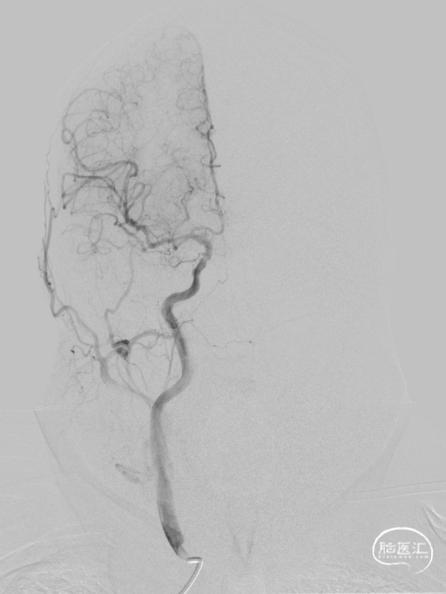

➢术后即刻影像

➢术后定期随访情况

术中造影证实右椎纤细、右椎V4段可见微弱血流入基底动脉、左椎动脉开口闭塞、颈升动脉通过侧支循环向左椎V3供血并逆流至V1中段、左椎V4轻度狭窄;